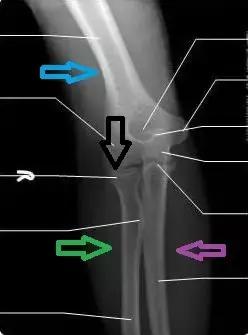

先说一下肘关节的解剖。我们的肘关节长这样:

通常我们说的上臂是指肱骨(蓝色箭头),前臂或者叫小臂包括两根骨头——尺骨(紫色箭头)和桡骨(绿色箭头),红色箭头指的是桡骨环状韧带,它像漏斗一样紧紧包裹住桡骨头(下图黑色箭头),防止桡骨小头脱出。

成年人的骨骼发育完善、韧带结实紧密,造就了强大的肘关节,足以负担我们全身的重量。但是——4岁以下的幼儿,桡骨头发育未全,环状韧带不够强劲,手臂伸直+被强力牵拉扭转时,环状韧带无力hold住发育不全的桡骨,于是——韧带撕裂、桡骨小头脱位——就像这样(黑色箭头)